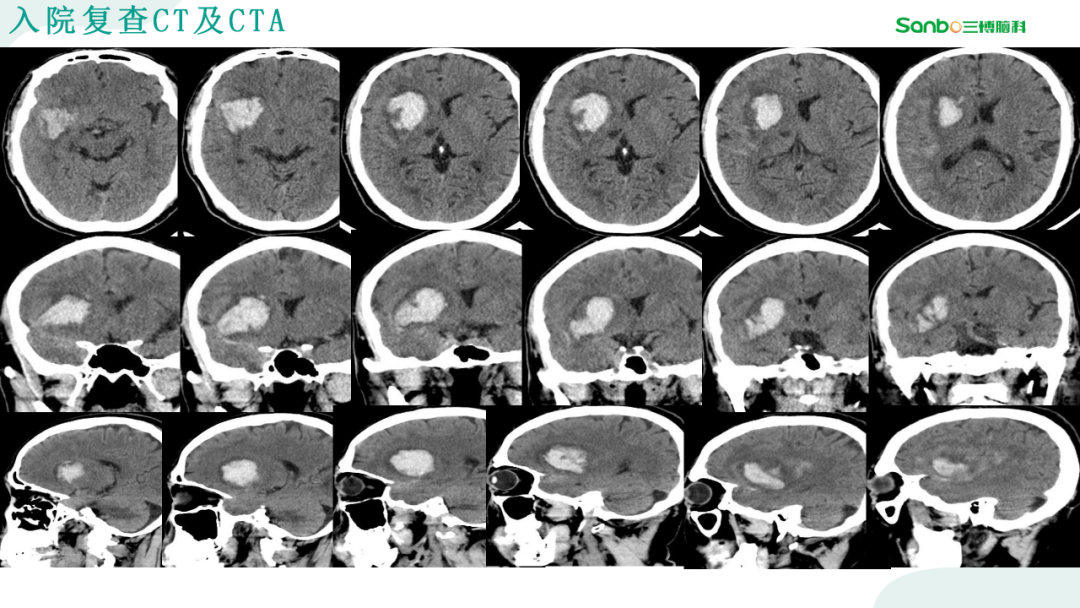

2月28日下午3:00,第二期“健康小课堂”科普活动由神外二科副主任杨海洋围绕《脑血管病的那些事》,给大家耐心讲解了有关脑血管的相关知识,生动的讲课引发在场的热烈讨论,大家纷纷表示受益匪浅。